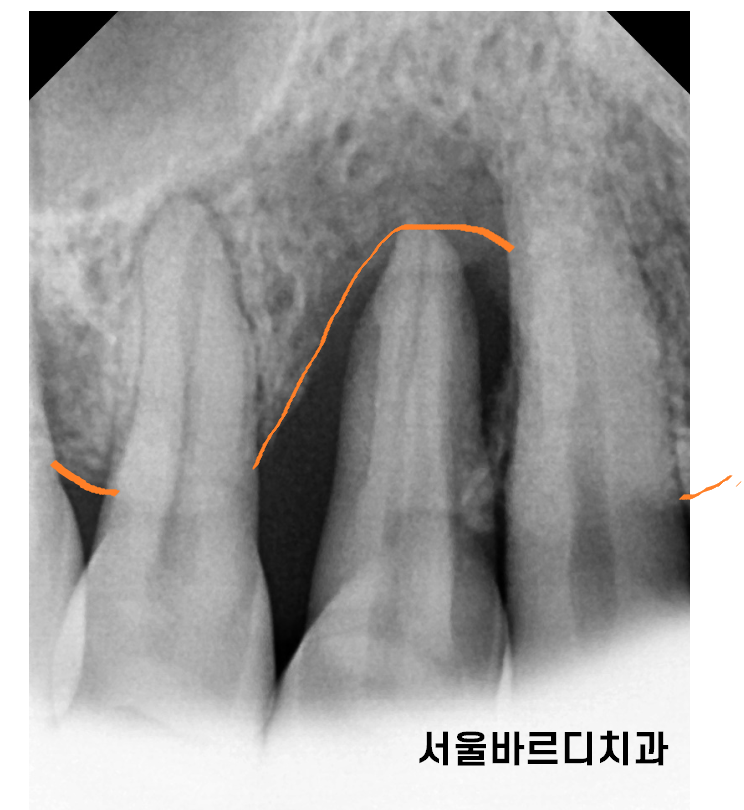

240712 대표적인 잇몸 뼈 녹음

대표적으로 치주 질환이 있습니다.

잇몸에 염증이 생기고

염증이기에 잇몸 뼈를 녹이는거죠~

초기에는 간단한 스케일링만으로도 해결이 되지만

잇몸 뼈 녹음이 한번 발생하면 절대 돌아오지 않습니다.

계속적인 관리를 통해 더 이상 녹지 않게 해주는 것 뿐이죠~